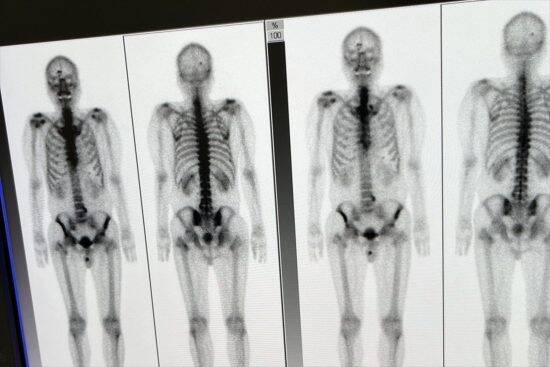

堀田さんは3泊にわたる検査を受け、その結果、医師からステージ4の前立腺がんであることを告げられた。がんは膀胱にも転移しており、ほぼ全身に広がっている状態だった。